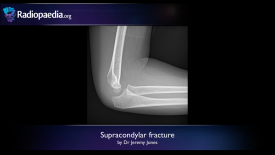

Supracondylar fracture – radiology video tutorial (x-ray) 0-0 screenshot

Supracondylar Fracture (Radiology Video X-Ray Tutorial)